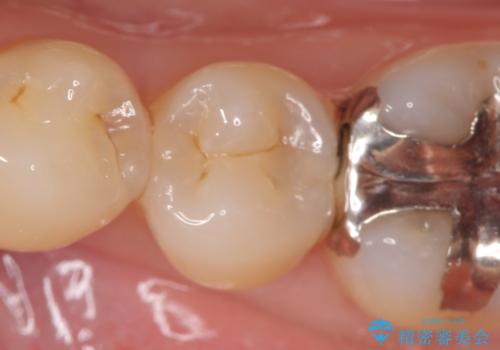

- 他院にて左下5の虫歯治療を行おうとしたところ、歯の神経治療をすると言われたため、できれば神経を残せないかと当院にいらっしゃった方の症例です。

自発痛・持続痛等の症状がなく、露髄(歯の神経が露出してしまうこと)することなく虫歯の除去を完了したため、しばらく経過観察を行った後に神経治療をすることなく、セラミックインレーによる修復を行うことができました。